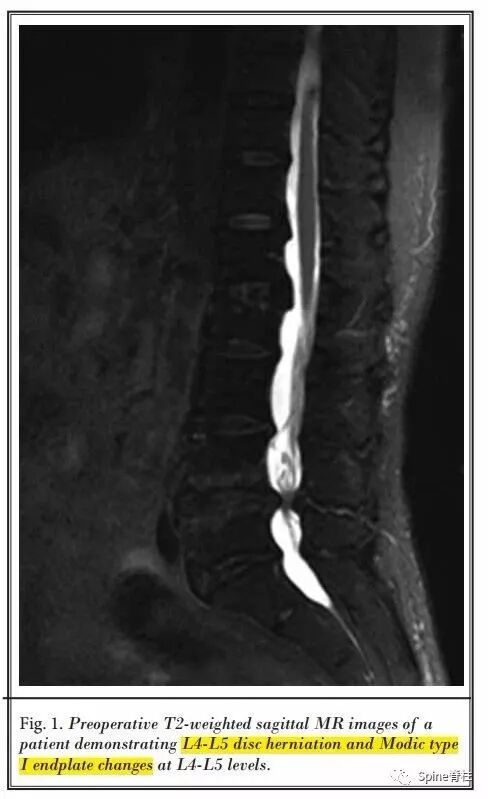

2017年,一篇来自中国(上海交通大学附属第六医院放射科)的研究,将PCD与经皮腰椎间盘切除术(percutaneous lumbar discectomy,PLD)相结合治疗症状性腰椎间盘突出症伴随终板Modic I型改变患者,取得了较好的效果。

-

此研究,评估了PLD+PCP治疗7例症状性腰椎间盘突出症伴随终板Modic I型改变患者,术后VAS和ODI评分明显改善,且无明显并发症的发生。

典型病例

最后作者总结,PLD+PCP可作为老年腰椎间盘突出症和Modic I型终板改变患者的可选治疗方法,对介入放射科医生来说是非常可行的。